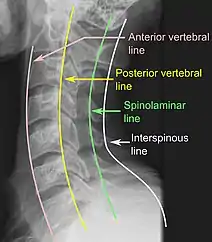

On CT scan or X-ray, a cervical fracture may be directly visualized. In addition, indirect signs of injury by the vertebral column are incongruities of the vertebral lines,[7] and/or increased thickness of the prevertebral space:[8]

X-ray of normal congruous vertebral lines

X-ray of normal congruous vertebral lines